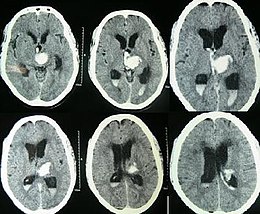

| Hydrocephalus as seen on a CT scan of the brain. The black areas in the middle of the brain (the lateral ventricles) are abnormally large and filled with fluid. | |

Hydrocephalus is a condition in which an accumulation of cerebrospinal fluid (CSF) occurs within the brain.[1] This typically causes increased pressure inside the skull. Older people may have headaches, double vision, poor balance, urinary incontinence, personality changes, or mental impairment. In babies, it may be seen as a rapid increase in head size. Other symptoms may include vomiting, sleepiness, seizures, and downward pointing of the eyes.[1]